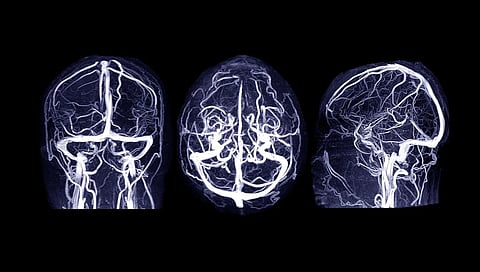

Bradley S. Peterson, M.D., from the Children's Hospital Los Angeles, and colleagues conducted a prospective, longitudinal pregnancy cohort study from January 1998 to July 2015 to identify associations of prenatal CPF exposure with brain structure, function, and metabolism in school-aged children. A total of 512 pregnant women of African American or Dominican descent had CPF levels measured at delivery. Offspring aged 6 years and older were approached for magnetic resonance imaging scanning (270 participants).

The researchers found a significant association for progressively higher prenatal CPF exposure levels with progressively thicker frontal, temporal, and posteroinferior cortices; reduced white matter volumes in these regions; higher fractional anisotropy and lower diffusivity in internal capsule white matter; reduced regional blood flow throughout the brain; lower indices of neuronal density in deep white matter tracts; and poorer performance on both fine motor and motor programming tasks in children.

"Blood flow is an important indicator of underlying metabolism -- the energy used by brain tissue. In my opinion, it's maybe the most important finding of the paper, because it says that globally there's a problem with brain metabolism in direct proportion to how much CPF exposure they had," Peterson said in a statement.